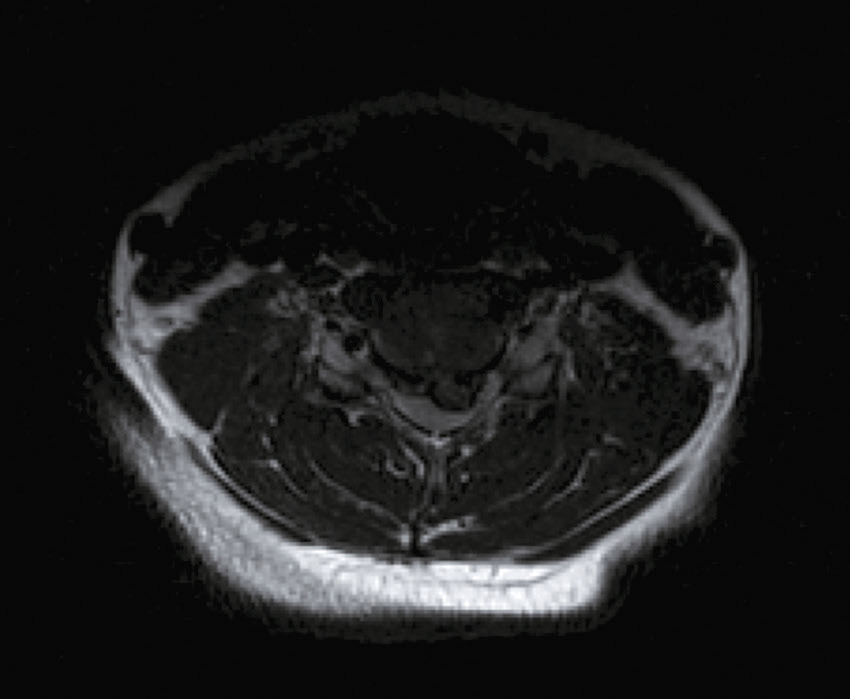

Vous faites réaliser une IRM cervicale (en séquence T2 sagittale et axiale) dont voici les résultats (fig. 31.14 et 31.15). Sur les images, que visualisez-vous ?

L'image semble être une coupe transversale obtenue par imagerie par résonance magnétique (IRM) d'une région anatomique du corps humain, probablement au niveau cervical (la région du cou). L'image montre une section horizontale vue de haut, avec des variations de densités grises correspondant aux différentes structures biologiques. Au centre de l'image, une structure ronde ou ovale de couleur foncée est visible, qui pourrait correspondre à une section de la moelle épinière ou du canal rachidien. Autour de cette zone centrale, on observe des couches de tissus avec des tonalités grises variées. Les couches musculaires paraissent bien délimitées, entourant les structures osseuses qui pourraient être les vertèbres cervicales. Ces dernières forment une structure plus claire et plus dense, de forme circulaire. L'image met aussi en évidence des zones sombres et homogènes autour des muscles, qui sont probablement des espaces remplis de fluides ou simplement des régions sans signal particulier dans cette technique d'imagerie. La qualité et les contrastes permettent de différencier les structures molles, musculaires, osseuses et nerveuses. Ce type d'imagerie est souvent utilisé pour visualiser des détails précis, comme les pathologies éventuelles des nerfs ou les anomalies structurelles dans cette région.

L'image montre une IRM de la colonne cervicale, qui est la partie supérieure de la colonne vertébrale située dans le cou. Sur cette image, on peut voir les vertèbres cervicales empilées les unes sur les autres, séparées par des disques intervertébraux. L'IRM permet de visualiser les structures internes avec une grande précision, y compris les os, les disques, la moelle épinière et les tissus mous environnants. Cette image est intéressante car elle peut révéler des anomalies telles que des hernies discales, des compressions de la moelle épinière ou d'autres pathologies qui pourraient causer des douleurs ou des dysfonctionnements neurologiques. Les vertèbres apparaissent comme des blocs rectangulaires sombres, tandis que les disques intervertébraux sont les espaces plus clairs entre eux. La moelle épinière, visible au centre, est entourée de liquide céphalo-rachidien, qui apparaît en blanc sur l'image. Cette IRM est un outil diagnostique essentiel pour les médecins afin d'évaluer l'état de la colonne cervicale et de planifier un traitement approprié si nécessaire.

- A compression médullaire cervicale

- B myélite cervicale

- C hernie discale C5-C6

- D syringomyélie

- E spondylodiscite cervicale